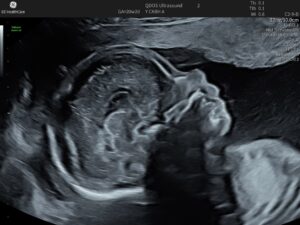

The Anatomy scan is a key milestone in your pregnancy and offers the most detailed check of your baby’s development. At this stage, your baby is large enough for a thorough examination and developed enough to show clear signs of growth and movement, providing valuable insights. The scan is also clear enough to capture detailed images, as your baby’s bones (which can block the ultrasound waves and therefore the picture) haven’t fully developed yet.

Generally performed between 19-21 week gestation, the scan ensures a comprehensive review of your baby’s development, including the skull, brain, face, chest, heart, stomach, kidneys, spine, limbs, and more. If you’d like, we can usually determine the baby’s sex at this stage. Additionally, we’ll check the amniotic fluid level and overall fetal proportions.

Seeing your baby move during the scan can be a comforting experience, particularly since you may not yet feel those movements, even though you might be asked about it frequently. By this stage, you might not have the same obvious symptoms to reassure you, so seeing your baby active on the screen can be a welcome reminder that everything is going well.